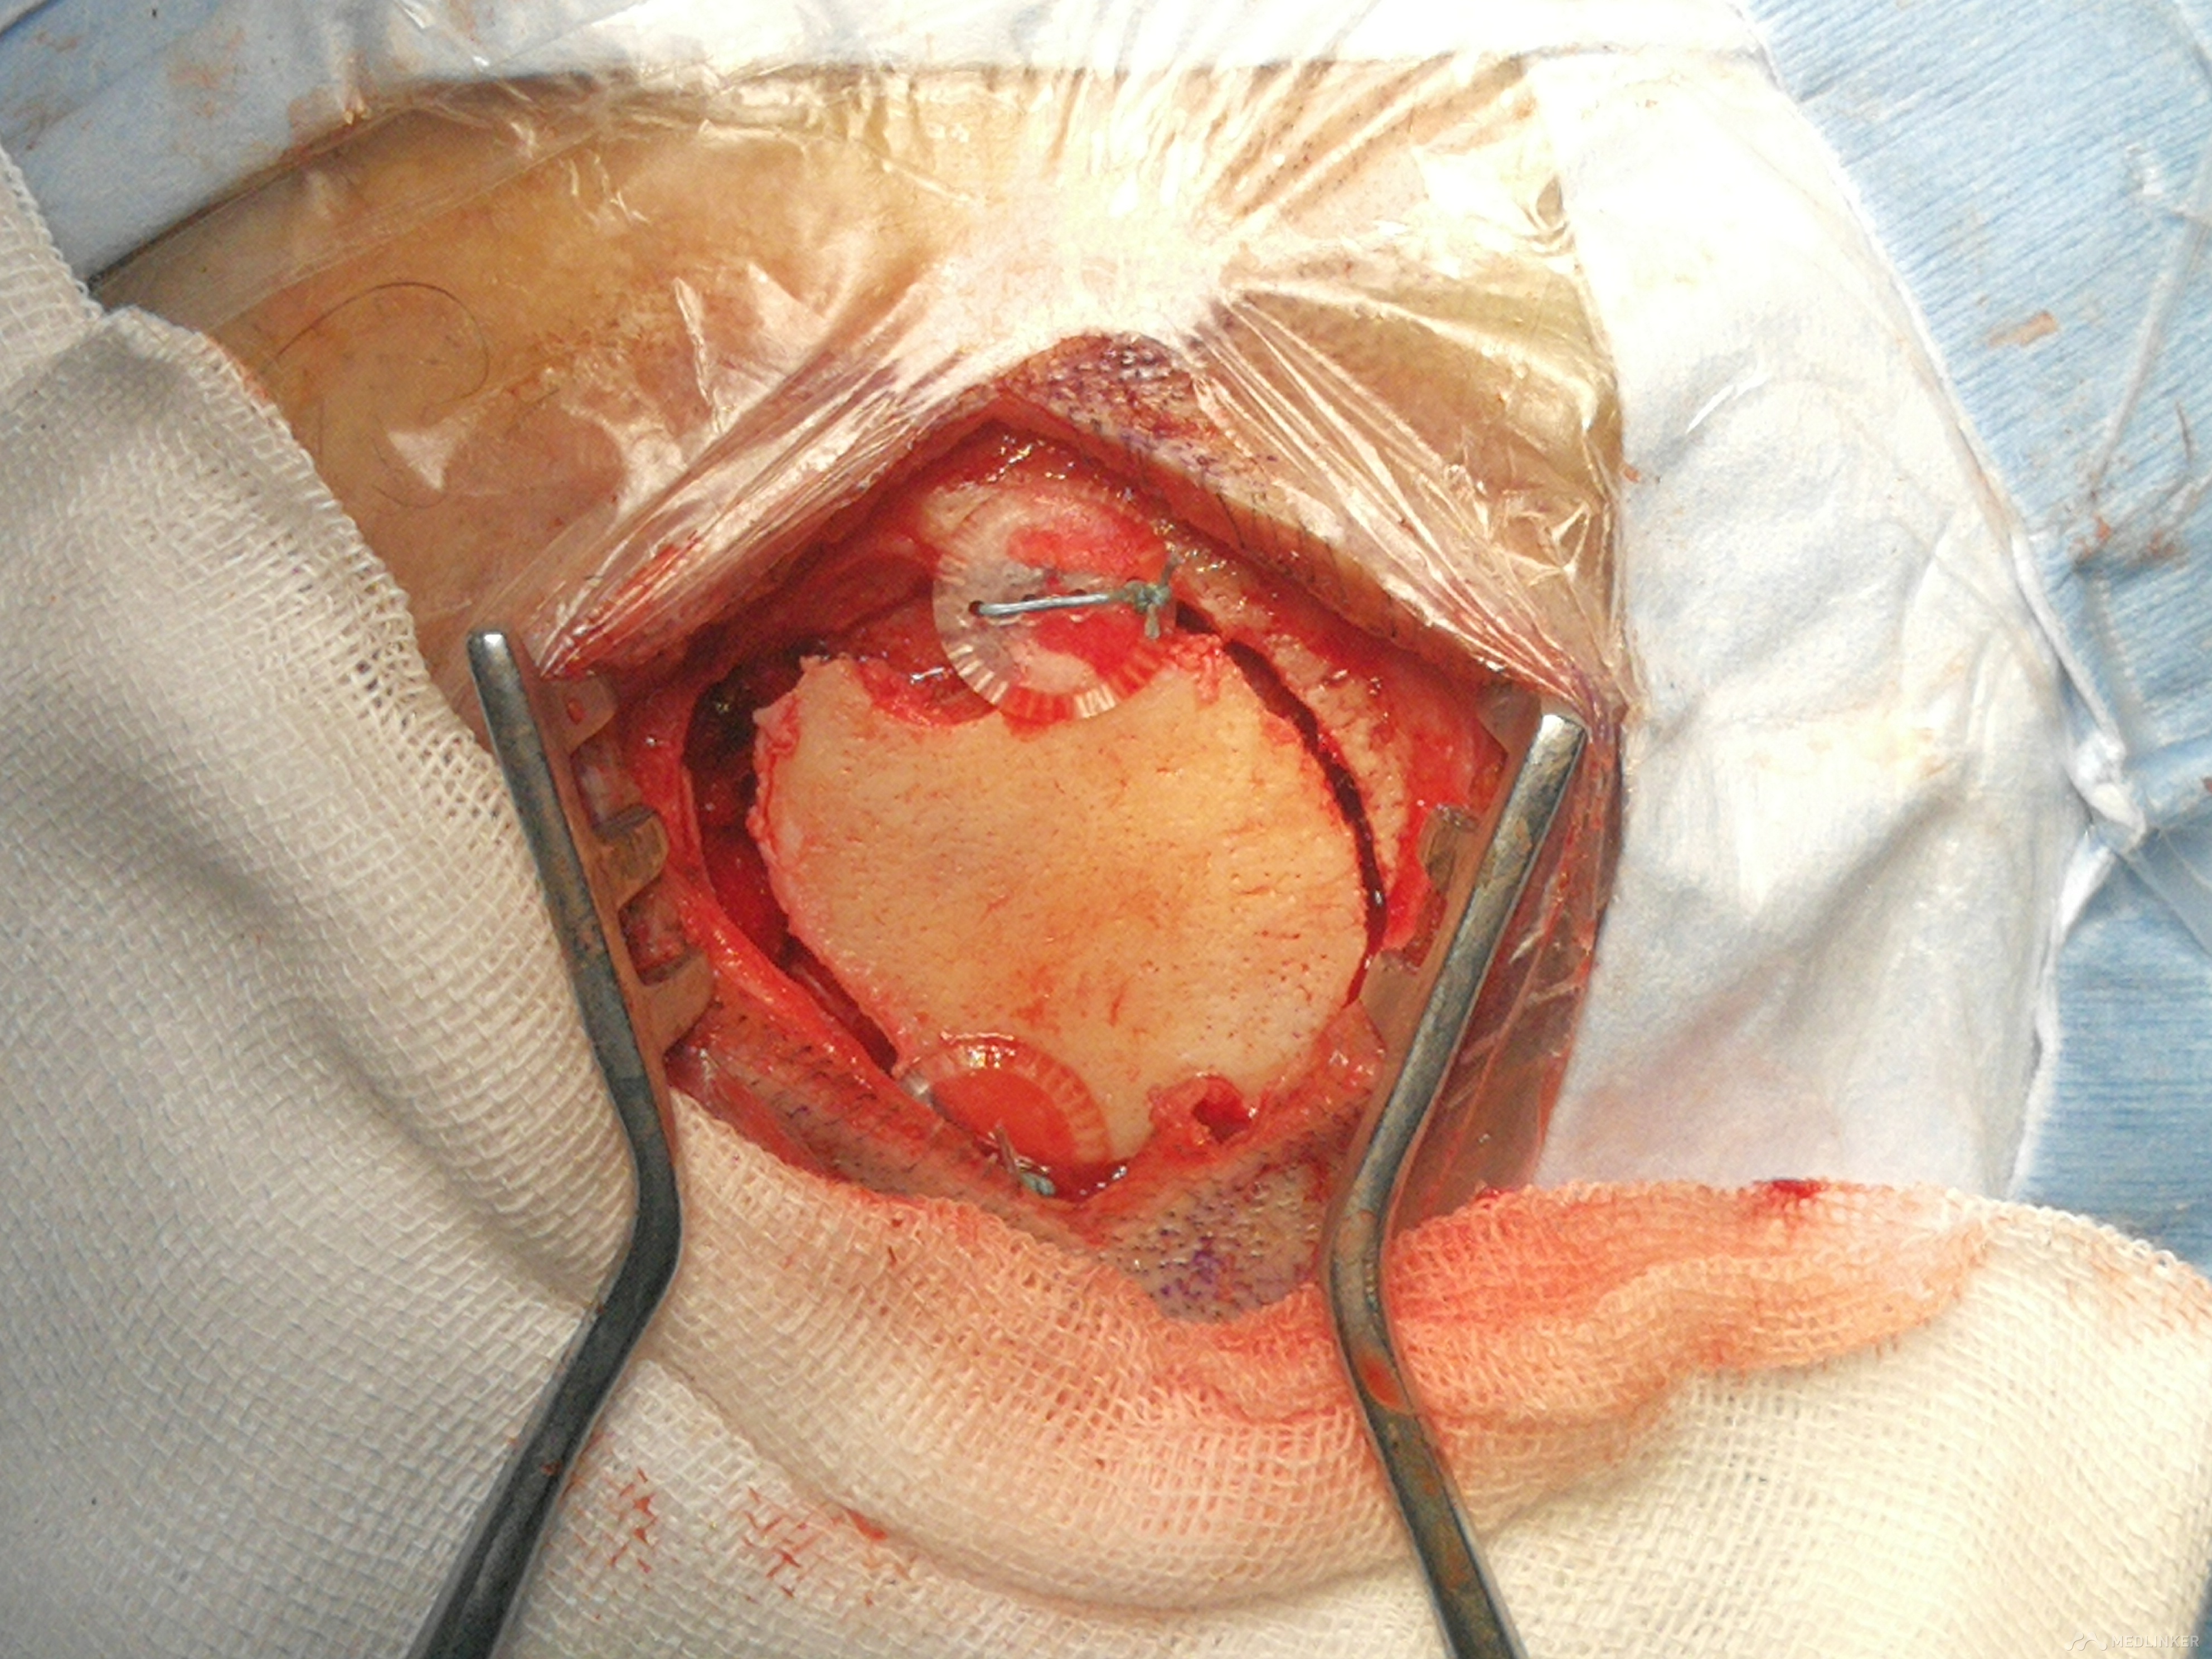

切开头皮保留骨膜 游离骨膜,以备修补硬脑膜

清除完血肿,严密缝合硬脑膜

还纳骨瓣